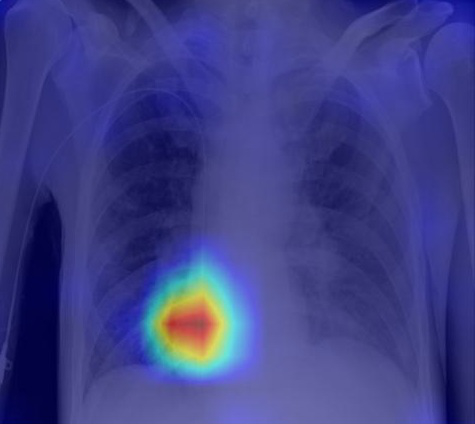

Recognizing normal/abnormal positioning of lines and tubes and their tips with answers derived from the AI attention heat map of a deep learning model

We have developed deep learning AI models trained on chest X-ray images focused on2 stages: (i) segmentation and (ii) classification of lines and tubes. A segmentation model generates masks for any lines and tubes present on a CXR image, which will then be fed to the classification model for identification of the type of line and the position of the tip.

Performance results for central venous catheter (CVC) and endotracheal tube (ETT) tip localisation:

A5 - fold cross-validation of the model was conducted using 5,867 images. The results showed that the classification model can accurately identify the position of the  tip as normal or abnormal, with an area-under-curve (AUC) of 0.902 for central venous catheters and 0.959 for endotracheal tubes.